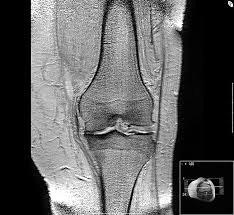

Artróza je onemocnění kloubů, jehož příčinou je nadměrné přetěžování s následným opotřebením kloubních ploch a postupným opotřebením chrupavek, které kloubní plochu tvoří. Po překročení určité hranice opotřebení pak dochází k podráždění celého kloubu.

Rozvoj artrózy bývá velmi pozvolný, obvykle trvá mnoho let až desítky let. Nejčastěji bývají postiženy klouby kolen a kyčlí.

Artróza je nejčastější onemocnění kloubů. Postihuje nejvíce kolenní a kyčelní klouby, postihuje však i další klouby (rameno, páteř, loket, prsty aj.).